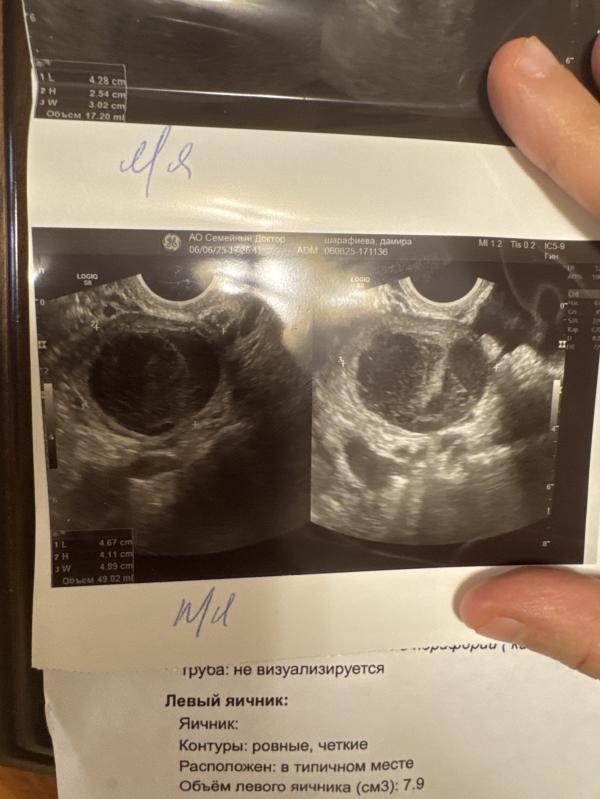

Выявили кисту желтого тела 40*36 мм,значит ждать новый цикл,беременность невозможна да?😢

Ну так беременность в самом начале питается от жёлтого тела. Смотря какой размер его. Что-то свыше 20-22мм , то беременность вероятнее всего есть